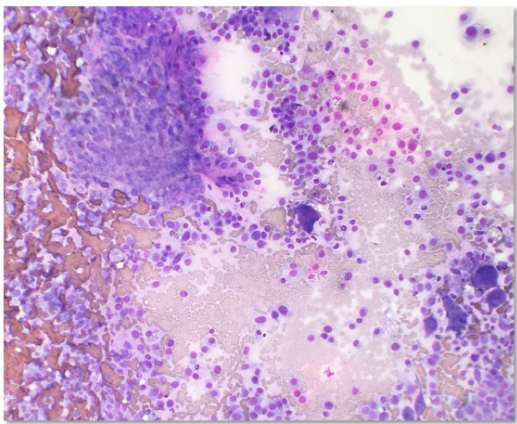

Diagnostics may include immunohistochemistry, special staining for ALP activity, flow cytometry and PARR. The latter two diagnostics are especially useful to evaluate lymphoid neoplasia, whether lymphoma or leukemia. In contrast to some mesenchymal cells, osteoblasts (the cell of origin for osteosarcoma) tend to exfoliate well (Fig. 1).

Classic cytologic descriptions of osteosarcomas may include moderate to high numbers of plump mesenchymal cells in a densely granular eosinophilic background with varying amounts of an extracellular pink wavy or amorphous matrix material in association with the neoplastic cells (Raskin and Meyer, 2016; Etzioni, 2022). Individual neoplastic cells are oval to rounded with moderately basophilic cytoplasm, with/without a perinuclear clearing/Golgi zone and flecks of atypical mitotic figures may be observed in some neoplastic and multinucleate cells. Nuclei are extremely eccentric, often appearing as if in the center of the cell, and are usually one to two prominent nucleoli.

Osteoclasts

The presence of osteoclasts must also be considered. When osteoclasts (Fig. 5) are seen, indicates bony lysis is likely occurring. However, bony lysis may occur in neoplastic and non-neoplastic lesions. With inflammation of the bone, lysis may occur. Thus, seeing this cell type does not constitute a diagnosis of neoplasia. Since osteoclasts are charged with cleaning up bone, variable numbers of them may be seen in osteosarcomas, mixed mammary tumors and osteomyelitis. They may also be a part of the process of remodeling bone during fracture healing and during normal growth in animals and humans. Additionally, giant cells may be mistaken for osteoclasts and may be a feature of feline and less commonly canine osteosarcomas cytologically and histopathologically (Pool, 1978).